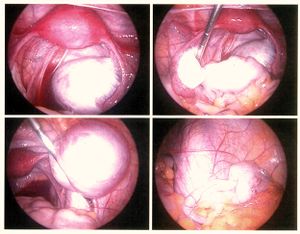

- عملية التنظير البطني: يعتبر من أهم الوسائل التشخيصية لهذا المرض حيث وجد أن 50% من النساء اللاتي لديهن الم أثناء الدورة الشهرية وألم في الحوض مصابات بداء البطانة الرحمية الهاجرة عند إجراء عملية التنظير.

- المنظار البطني لغرض إزالة البطانة الهاجرة بواسطة الحرارة أو الليزر وإزالة الالتصاقات و أكياس الدم وغالبا ما يستخدم عندما تكون المرأة في سن الخصوبة وترغب بإنجاب الأطفال.